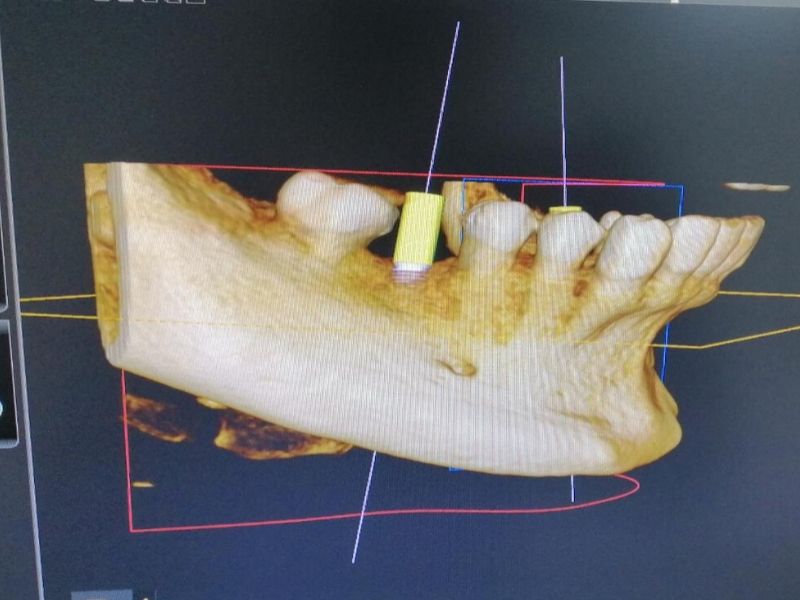

Tras realizar la valoración pertinente, le tomamos al paciente un registro en 3D Tac Dental (CBCT) con la finalidad de analizar y programar al detalle la colocación de los implantes. Es un paso necesario previo al comienzo del tratamiento, que nos ayuda a planificar los pasos a seguir y a determinar los plazos.

Finalmente, con todo listo para reponer las piezas dentales ausentes, se procede a la preparación de todo el instrumental técnico necesario y a realizar la cirugía de colocación de los implantes. Paso a paso, un poco más cerca de finalizar el tratamiento y devolver al paciente a su mejor estado de salud bucodental.